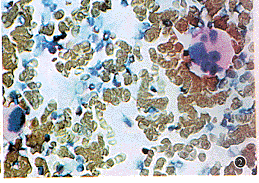

使用免疫组织化学方法和单克隆抗体(CD36抗体和PDGF-β受体抗体),分别证实骨髓巨核细胞表达TSP受体(CD36)和PDGF-β受体(图1,2)。

图1人骨巨核细胞表达CD36抗原骨髓涂片巨核z细胞对CD36单克隆抗体呈现强阳性反应。免疫组化方法,苏木素复染*200

图2人骨髓巨核细胞表达血小板源性生长因子(PDGF-B)受体。骨髓涂片风起云涌 个巨核细胞对PKGF-B受体单克隆抗体呈阳性反应。免疫组化方法,苏木素复杂,*200